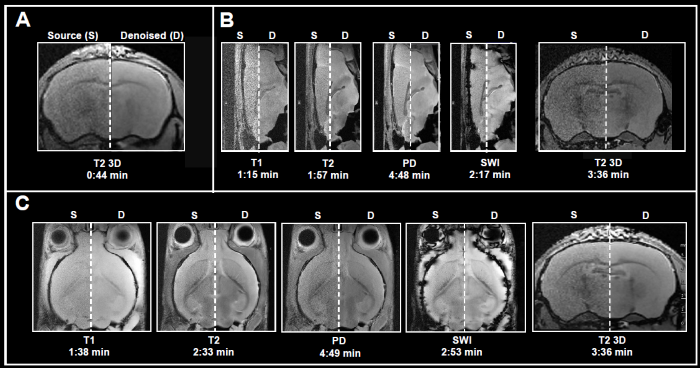

Obtaining MRI data is a slow process, and acquisition times increase alongside higher spatial resolution when extensive volumetric coverage is needed and/or multiple contrast images or quantitative data sets are gathered. Acquiring high SNR data in a reasonable amount of time is highly sought after. Here, Bruker showcases the use of Smart Noise Reduction to denoise fast structural brain scans.

Fig. 4 displays examples of ex vivo brain scans of different contrasts and orientations gathered in less than 5 minutes. The data was obtained from 3, 7, and 9.4 Tesla tools. To achieve the desired short acquisition time, standard protocols prepared for each system were improved by removing averaging, as seen in Fig. 4A-C.

This resulted in 7-15 times faster acquisition times compared to the original protocols. Yet, given the chosen resolution, no averaging resulted in noisy images. Reconstructing the obtained data with the denoising algorithm successfully removed noise from images and delivered high-quality images.

Figure 4. Examples of fast brain scans. Ex vivo data of a fixed mouse head acquired with different image contrasts, geometries and orientations. Data were acquired at A) 3 Tesla, B) 7 Tesla, and C) 9.4 Tesla. Images were reconstructed with no denoising (Source) and with a network Strong and applying 50% pre-denoising and a denoising level of 70% (Denoised). Image Credit: Bruker BioSpin Group